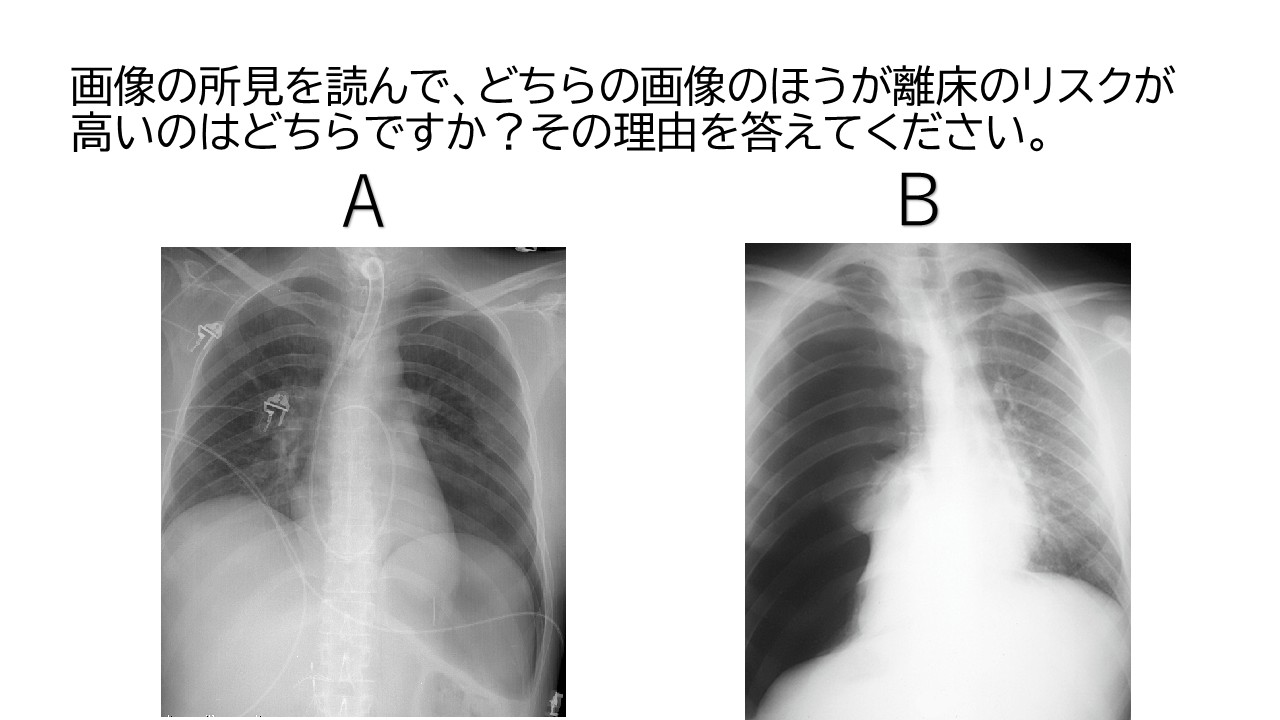

2つの画像のうち離床のリスクが高いのはどちらでしょうか?分からないという方は、下記講座の適応あり!

Bの方が重度の気胸が疑われるため、離床のリスクが高いと考えられる。

※上記、肺水腫・間質性肺炎の画像判読講座では詳しく解説します。

画像提供:radiopaedia.org